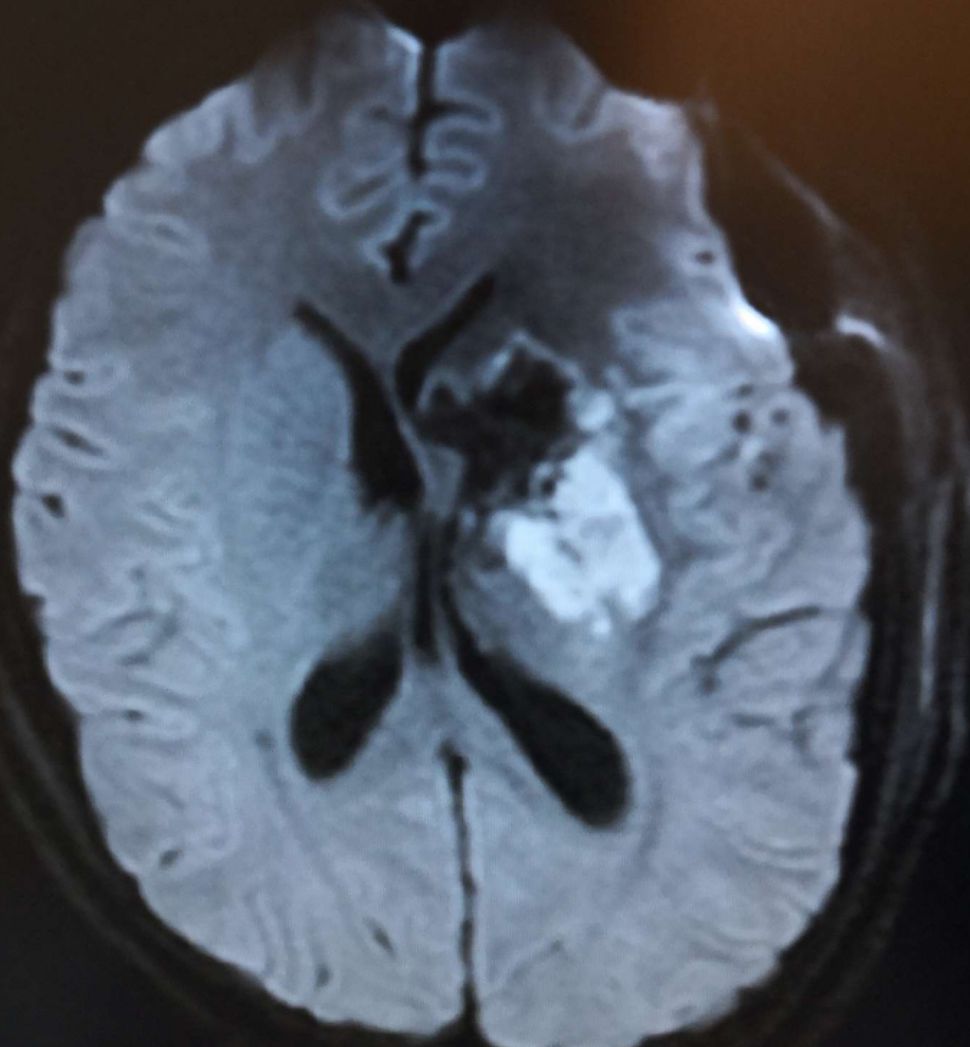

术前头颅MRI DWI显示:左侧基底节巨大占位病灶(49*53mm),呈高、低信号,脑室受压,中线移位明显。